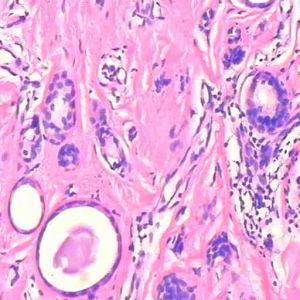

鏡下腫瘤組織自表皮基底層長出,伸向真皮或間質,輪廓如棒狀,或不規則地圖形分布。在細胞團巢的外線為柵欄狀排列的一層細胞,呈柱形,梭長桿形、深色,其長軸呈柵欄狀排列,相當於表皮的基底細胞。在中央部分的細胞,核呈卵形,胞質也不多;有的含較多色素而呈深色。組織結構多種多樣,有的呈巢團狀,巢內有角化珠;也有巢內出現腺腔樣空隙;有的細胞巢團與表皮基層相連,有的接近毛囊形狀。不管哪一種都具有一特徵,即瘤組織邊緣部總有一層柵狀排列的基底狀細胞。有的瘤組織被周圍纖維組織擠壓成索條狀則稱硬化型。這種癌有局部浸潤的行為,但一般不發生轉移,為低度惡性。如癌灶中部分為鱗狀細胞癌則稱為基底鱗狀細胞癌,其惡性程度是根據這部分鱗狀細胞癌的分化程度而決定。組織學上基底細胞癌應與皮膚汗腺癌和毛髮癌區別,汗腺瘤有2層細胞排列特點,毛髮癌有始基毛囊的結構。這兩者皆無邊緣柵狀排列的基底細胞層的特徵。此外尚應與基底樣細胞癌鑑別,後者發病年齡較輕,組織學上有挖空細胞,對HPVDNA的檢測呈陽性結果,這些是基底細胞癌所缺乏的。